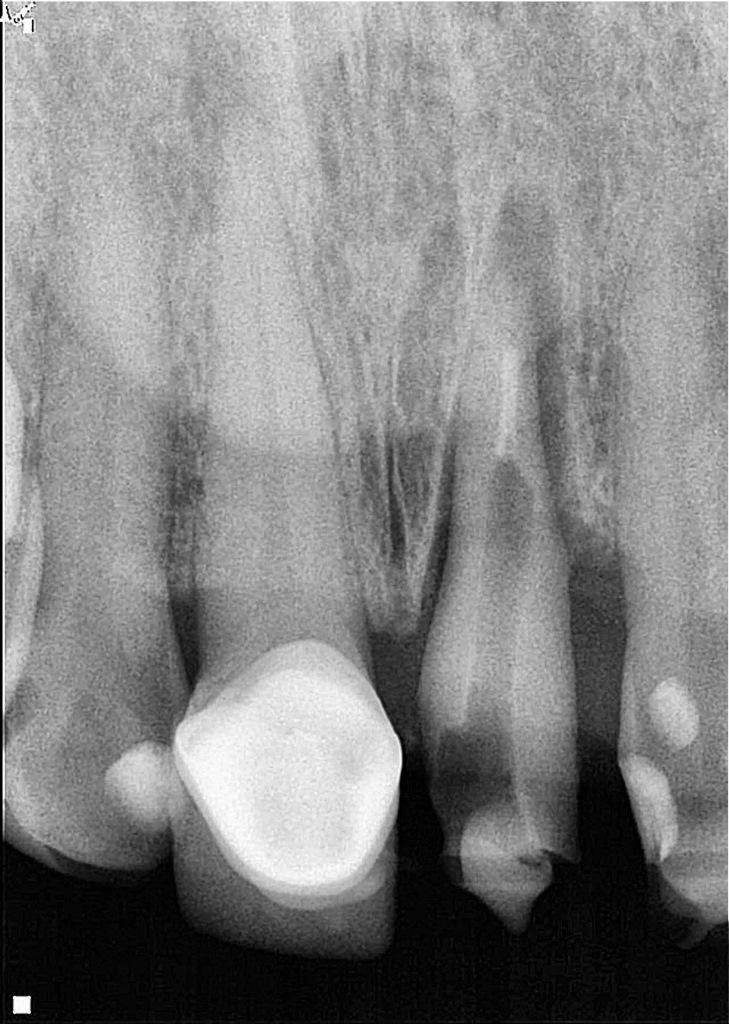

У пациентки случилась травма зубов верхней челюсти. У нее был косой перелом от мезиальной до дистальной части левого центрального резца верхней челюсти на поддесневом уровне. Штифт и металлокерамическая коронка были подвижны. Периапикальная ткань зуба была здоровой (фото 1). При рентгенологическом и клиническом обследовании было отмечено, что структура зубов недостаточна для предсказуемого восстановления. Планирование лечения включало измерение и анализ длины корня, ширины стенок корневого канала и имеющейся наддесневой структуры. Для сохранения зуба были рассмотрены различные варианты лечения, и после всесторонней оценки хирургическая экструзия была выбрана в качестве предпочтительного варианта для достижения адекватной здоровой наддесневой структуры зуба, тем самым предлагая пациентке благоприятное долгосрочное решение для лечения.

Фото 1: Первичная клиническая рентгенограмма, на которой показан зуб 21 с предыдущим лечением корневого канала, штифтом, полной коронковой реставрацией и косым переломом от мезиальной к дистальной части.